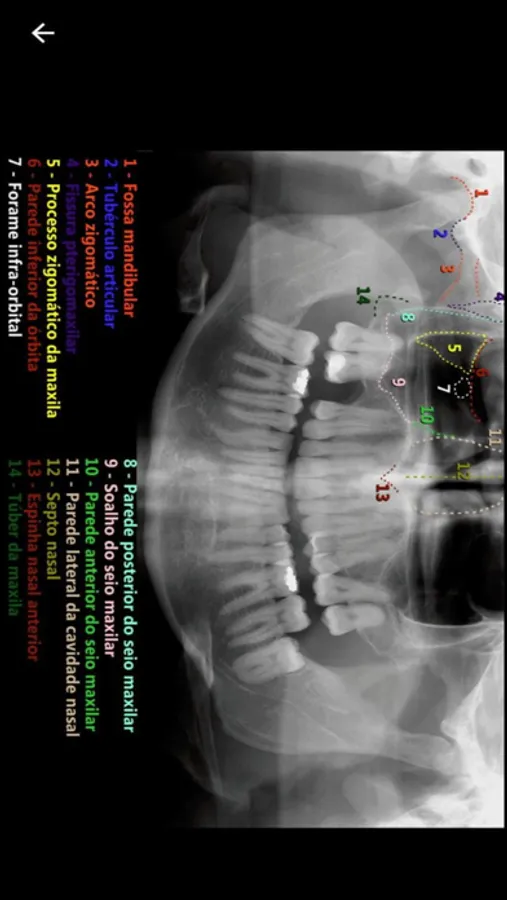

• Anatomia